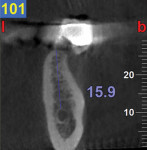

A CBCT study shows hard tissues and the shadow of soft tissues as long as they are surrounded by hard tissue. The pulpal tissue of the teeth is not visible, but the outline of the pulp chamber is visible. The mandibular nerve is not visible, but the cortical bone surrounding it does appear on the CBCT, making it possible to deduce where the mandibular nerve is expected to be. The proposed visualization technique allows very strong contrast to create a negative, much like the just-discussed image of the mandibular nerve. The concept is rather simple; VPS impression material can be radiopaque, but not all materials are radiopaque to the same extent, and some are not radiopaque at all (Figure 2). The patient wears a VPS impression during the CBCT exposure (Figure 3 and Figure 4). This can be the actual impression, or a dedicated impression made from a diagnostic cast (Figure 5). This simple technique shows a very distinct space, which is visible between the VPS material and the bone (Figure 6 and Figure 7). For the purpose of the 3D Click Guide fabrication, this space would otherwise be measured with the bone-sounding technique, as discussed in Part 1 of this series. Because the surface of the VPS impression visible in the CBCT image is exactly similar to the surface of the cast, the two can be exactly superimposed. Within the CBCT software, simple measurements can be made. Those measurements are made at the same locations as those used when bone sounding. Those measurements are then transferred to the cast. Additional information—eg, location of the mandibular canal—can be extrapolated and drawn as needed (Figure 8 and Figure 9).

An 80-year-old woman, who presented with a missing lower molar, requested an implant-supported replacement. Advanced periodontal bone loss at site No. 19 resulted in considerable resorption of the alveolar ridge after healing. Although simple bone sounding is the preferred data-gathering technique for the author, in this case, there was insufficient information available to safely perform an osteotomy. The decision was made to gather additional information with a CBCT study.

The cast was sectioned 4 mm distal of tooth No. 20. The data from the corresponding cross-sectional cut were transferred to the cast. The ideal buccolingual axis was drawn onto the cast, based on a screw access hole in the central fossa of the future crown. A small hole was drilled at the desired location of the shoulder of the implant. The pin of the Bucco Lingual Positioner (BLP) was placed in the hole, and the central groove of the BLP was lined up with the drawn implant axis. A drop of fast-setting cyano-acrylate glue was applied to lock the BLP in place (Figure 11). The opposing part of the cast was adjusted and the cast was reassembled into the Accu-trac tray. At this point, the buccolingual axis and the top of the implant were irreversibly set, and the mesiodistal could be determined without the risk of making inadvertent changes in the buccolingual plane. The correction slot in the crossbar of the wing assembly fits snugly over the top of the BLP, allowing mesiodistal rotation and mesiodistal translation (Figure 12). Once the correct mesiodistal position was selected, the wings were irreversibly connected to the vacuformed carrier by means of ortho-acrylic (Orthoresin, DENTSPLY International, www.dentsply.com); then the cross-sectional bar was removed, allowing placement of a rotation block. The surgical guide was placed in the mouth and a periapical radiograph was exposed (Figure 13). Note that if the buccal and lingual wings overlap and appear to be one, the radiograph has been taken exactly perpendicular to the ridge, allowing a decision to be made because the image is of acceptable diagnostic quality. In this case, the trajectory was as desired, and the 0º rotation block was selected, as there was no need for rotation adjustments by means of the 3º or 7º rotation blocks (Figure 14). The surgical guide was sterilized in a cold sterilizing solution and the surgery was performed per the manufacturer’s drilling protocol. A 8.5-mm x 4.3-mm implant (NobelActive™ 4.3 x 10 mm, Nobel Biocare, www.nobelbiocare.com) was placed as planned (Figure 15).